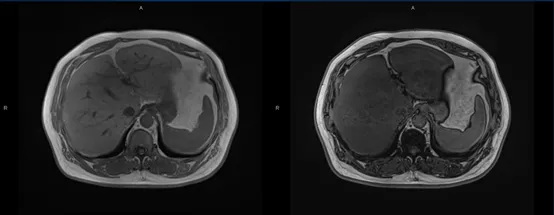

体检客户:男,56岁,常年患有糖尿病,超声检查发现脂肪肝,后进行肝脏MR定量分析检查。

多回波DIXON技术:分割全肝扫描定量分析,肝脏存在脂肪浸润,全肝肝脏脂肪含量平均为18.4%,ROI区域内肝脏脂肪含量平均为16.3%;HISTO序列波普分析:感兴趣区内测定肝脏脂肪含量为21.4%。

结论:全肝脂肪定量分析提示肝脏脂肪浸润,结合波普感兴趣区测定肝脏脂肪含量,综合考虑为中度脂肪肝(≥10%且<25%)。

用药3个疗程后,再次复查,肝脏平均脂肪含量减少,感兴趣区肝脏脂肪含量减少,数据表明用药具有效果。